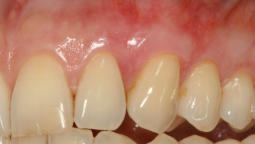

Mikrochirurgischer Wundverschluss

Gingivatransplantat fixiert

Zustand 3 Wochen post OP